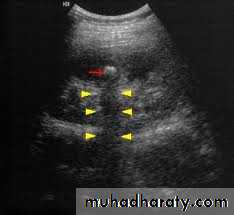

2-Stones larger than 5mm are easily seen on US but smaller ones may be missed.

-They produce intense echoes (hyperechoic) and cast acoustic shadows.

-Proximal and distal ureteric dilatation can be easily identified unlike mid-ureteric dilatation, and stones located in the middle third of the ureter are hard to be demonstrated unlike upper and lower ureteric stones (especially those lodged in the vesico-ureteric junction or pelvi -ureteric junction) which are easily identified by ultrasound.